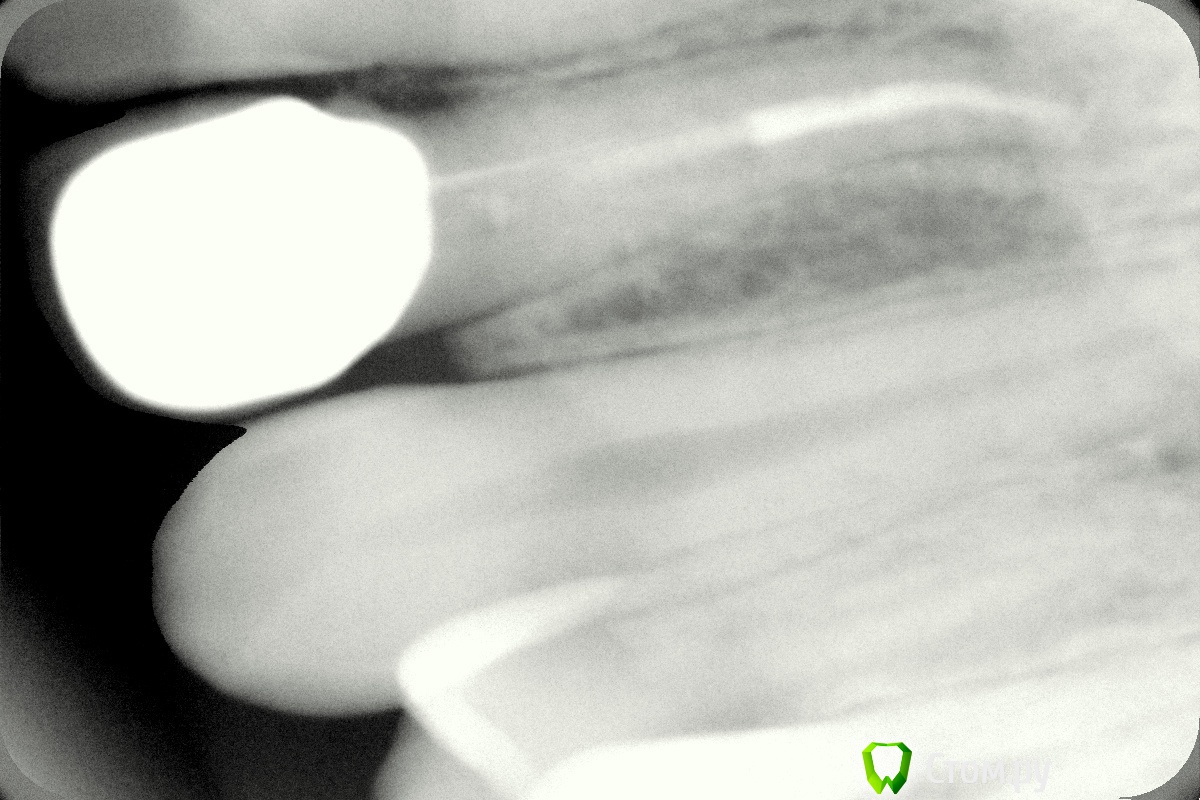

johniola Опубликовано 5 февраля, 2014 Поделиться Опубликовано 5 февраля, 2014 Девочка 19 лет из церковного приюта(иногда помогаю),22 зуб анкер+композит+хр периодонтитФото с свш +билд ап не нашёл,проостите Ссылка на комментарий